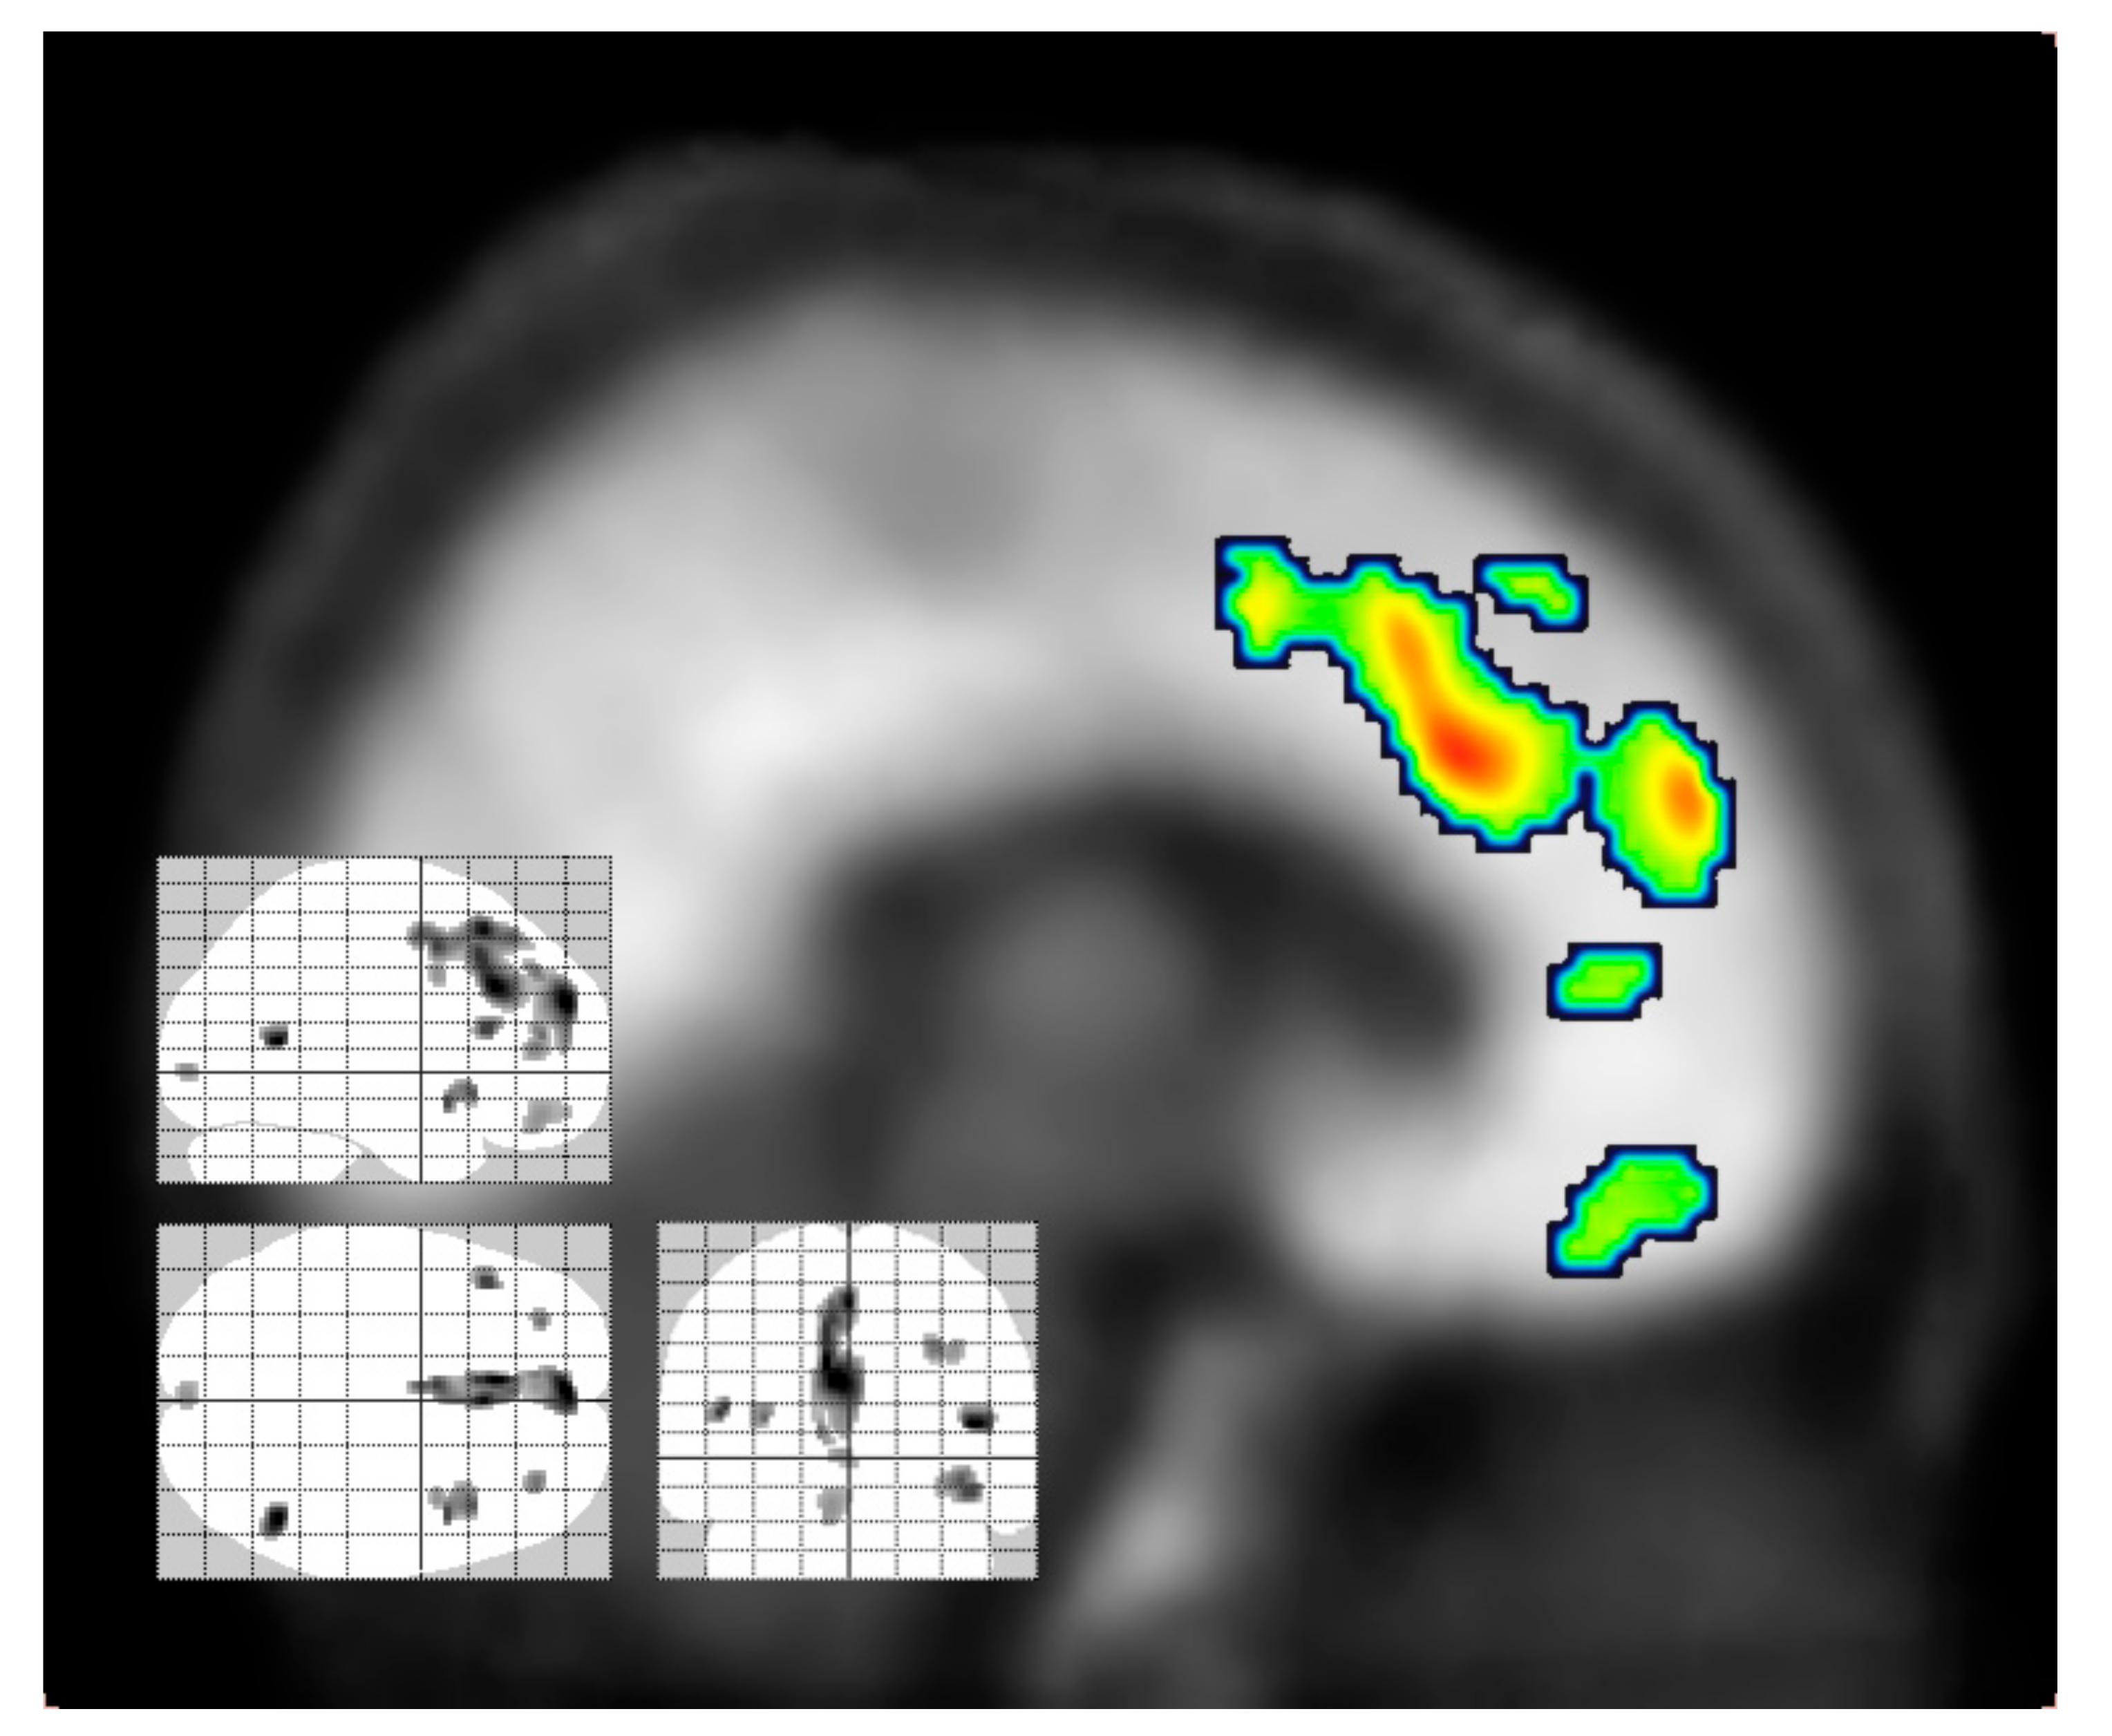

- Madsen, M.K.; Fisher, P.M.; Burmester, D.; Dyssegaard, A.; Stenbaek, D.S.; Kristiansen, S.; Johansen, S.S.; Lehel, S.; Linnet, K.; Svarer, C.; et al. Psychedelic effects of psilocybin correlate with serotonin 2A receptor occupancy and plasma psilocin levels. Neuropsychopharmacology 2019, 44, 1328–1334. [Google Scholar] [CrossRef]

- Stenbaek, D.S.; Kristiansen, S.; Burmester, D.; Madsen, M.K.; Frokjaer, V.G.; Knudsen, G.M.; Fisher, P.M. Trait Openness and serotonin 2A receptors in healthy volunteers: A positron emission tomography study. Hum. Brain Mapp. 2019, 40, 2117–2124. [Google Scholar] [CrossRef]